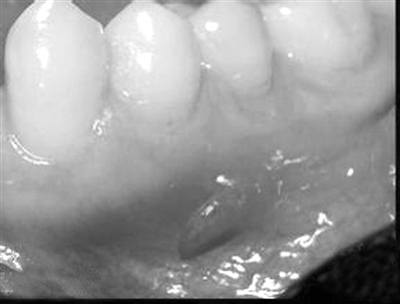

Lwgnyez Nohheuj Doz Nong Gawhfoeg Baenzlawz Guh

小孩牙龈脓肿怎么办

Lwgnyez nohheuj doz nong gawhfoeg rox gamjdaengz daegbied in dot, lienz daengz yungh yw dingz in cungj fouzfap vanjgaij. Heujcij danghnaeuz doz nong gawhfoeg mbouj ndaej gibseiz yw ndei, rox yingjyangj daengz gij heujgungx yaek sengmaj okdaeuj haenx; danghnaeuz dwg heujgungx doz nong gawhfoeg, mboujdanh in dot nanz dingj, caemhcaiq cauhbaenz heuj lon heuj loenq dem.

Raen lwgnyez nohheuj doz nong gawhfoeg seiz, cawjranz ndaej baenz- neix bae cawqleix:

1、Cam lwgnyez gizlawz heuj doz nong gawhfoeg. Heuh lwgnyez aj bak, cazyawj gizde nohheuj dwg mbouj dwg ndingfoeg.